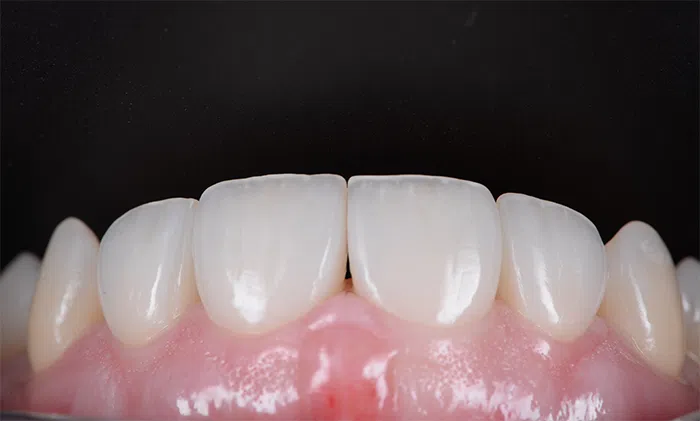

După

Caz de estetică dentară – Coroane ceramică presată E-Max

Provocarea acestui caz a fost tratarea minim invazivă a dinților restanți, în urma înlocuirii coroanelor vechi și obținerea unor dinți cu un volum mai mare pentru echilibrarea zâmbetului într-un aspect cat se poate de natural.

Pacientă a beneficiat de corecție gingivală cu laser pentru uniformizarea asimetriilor gingivale, tratamente endodontice de canal sub microscop, obturațiile vechi (plombe) schimbate cu materiale de compozit cu particule nanoceramice, și fațete dentare din ceramică presată E-Max.

Termen de finalizare 2 săptămâni de la amprentarea finală.